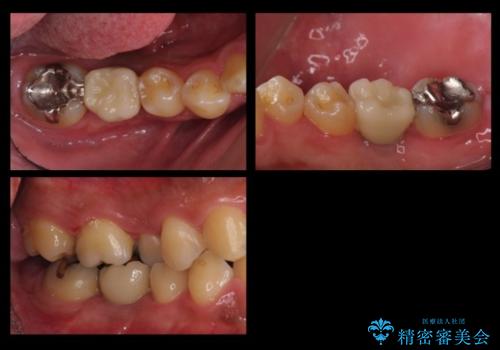

- 右下の奥歯にインプラントを入れたいと来院。

抜歯から時間が経っており、骨が十分あったためすぐにインプラントを入れることが可能でした。骨も補う必要がありませんでした。

インプラントの術式は比較的単純で、難しくないですが、予後を見据えて角化歯肉を増やす手間をかけることが大変重要です。

長期的な予後を見据えた治療をしてもらえる病院を、慎重に選んでいただくことをお勧めします。